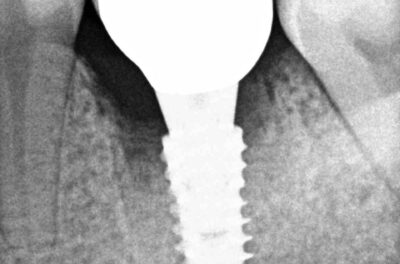

Специализация: терапия(эндодонтия), ортопедия, имплантология.